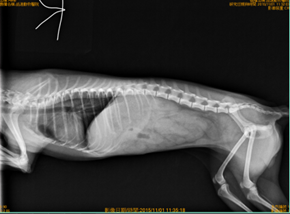

體溫正常,但是肛溫套上都是有著血液的糞便,透過血液檢查跟X光檢查確診為【急性胰臟炎】

右側及腹背的X光,消化道都無任何食物。